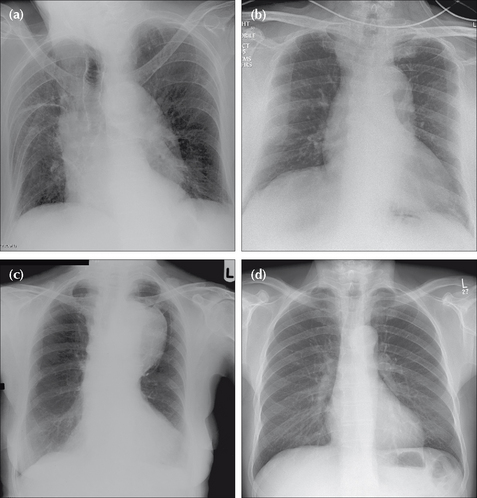

Figure 24.4 A widened mediastinum at the level of the aortic arch may be vascular and due to either age related unfolding of the aorta (b), aortic dissection (c) or an aneurysm (d). A normal aorta—no unfolding—is shown in (a). Age related unfolding of the ascending and descending aorta from early middle age is a common CXR finding. Any unfolding will appear exaggerated, and often worrying, on an AP CXR because of the magnification effect.

Figure 24.5 Four patients, all middle-aged or elderly. Patient (a): age related aortic unfolding. Patient (b): the aortic shadow at the level of the ascending aorta and aortic arch is prominent in this patient who presented with tearing chest pain. Stanford Type A dissection. Patient (c): the aortic arch and the proximal descending aorta are very prominent and due to aneurysmal dilatation. Patient (d): a normal aortic outline—no unfolding. The amount of age related unfolding of the thoracic aorta shows a wide variation in middle-aged or elderly individuals—compare the CXRs of patient (a) and patient (d). Furthermore, in an elderly or frail patient, rotation (see patient a) is often present and will exaggerate any unfolding.